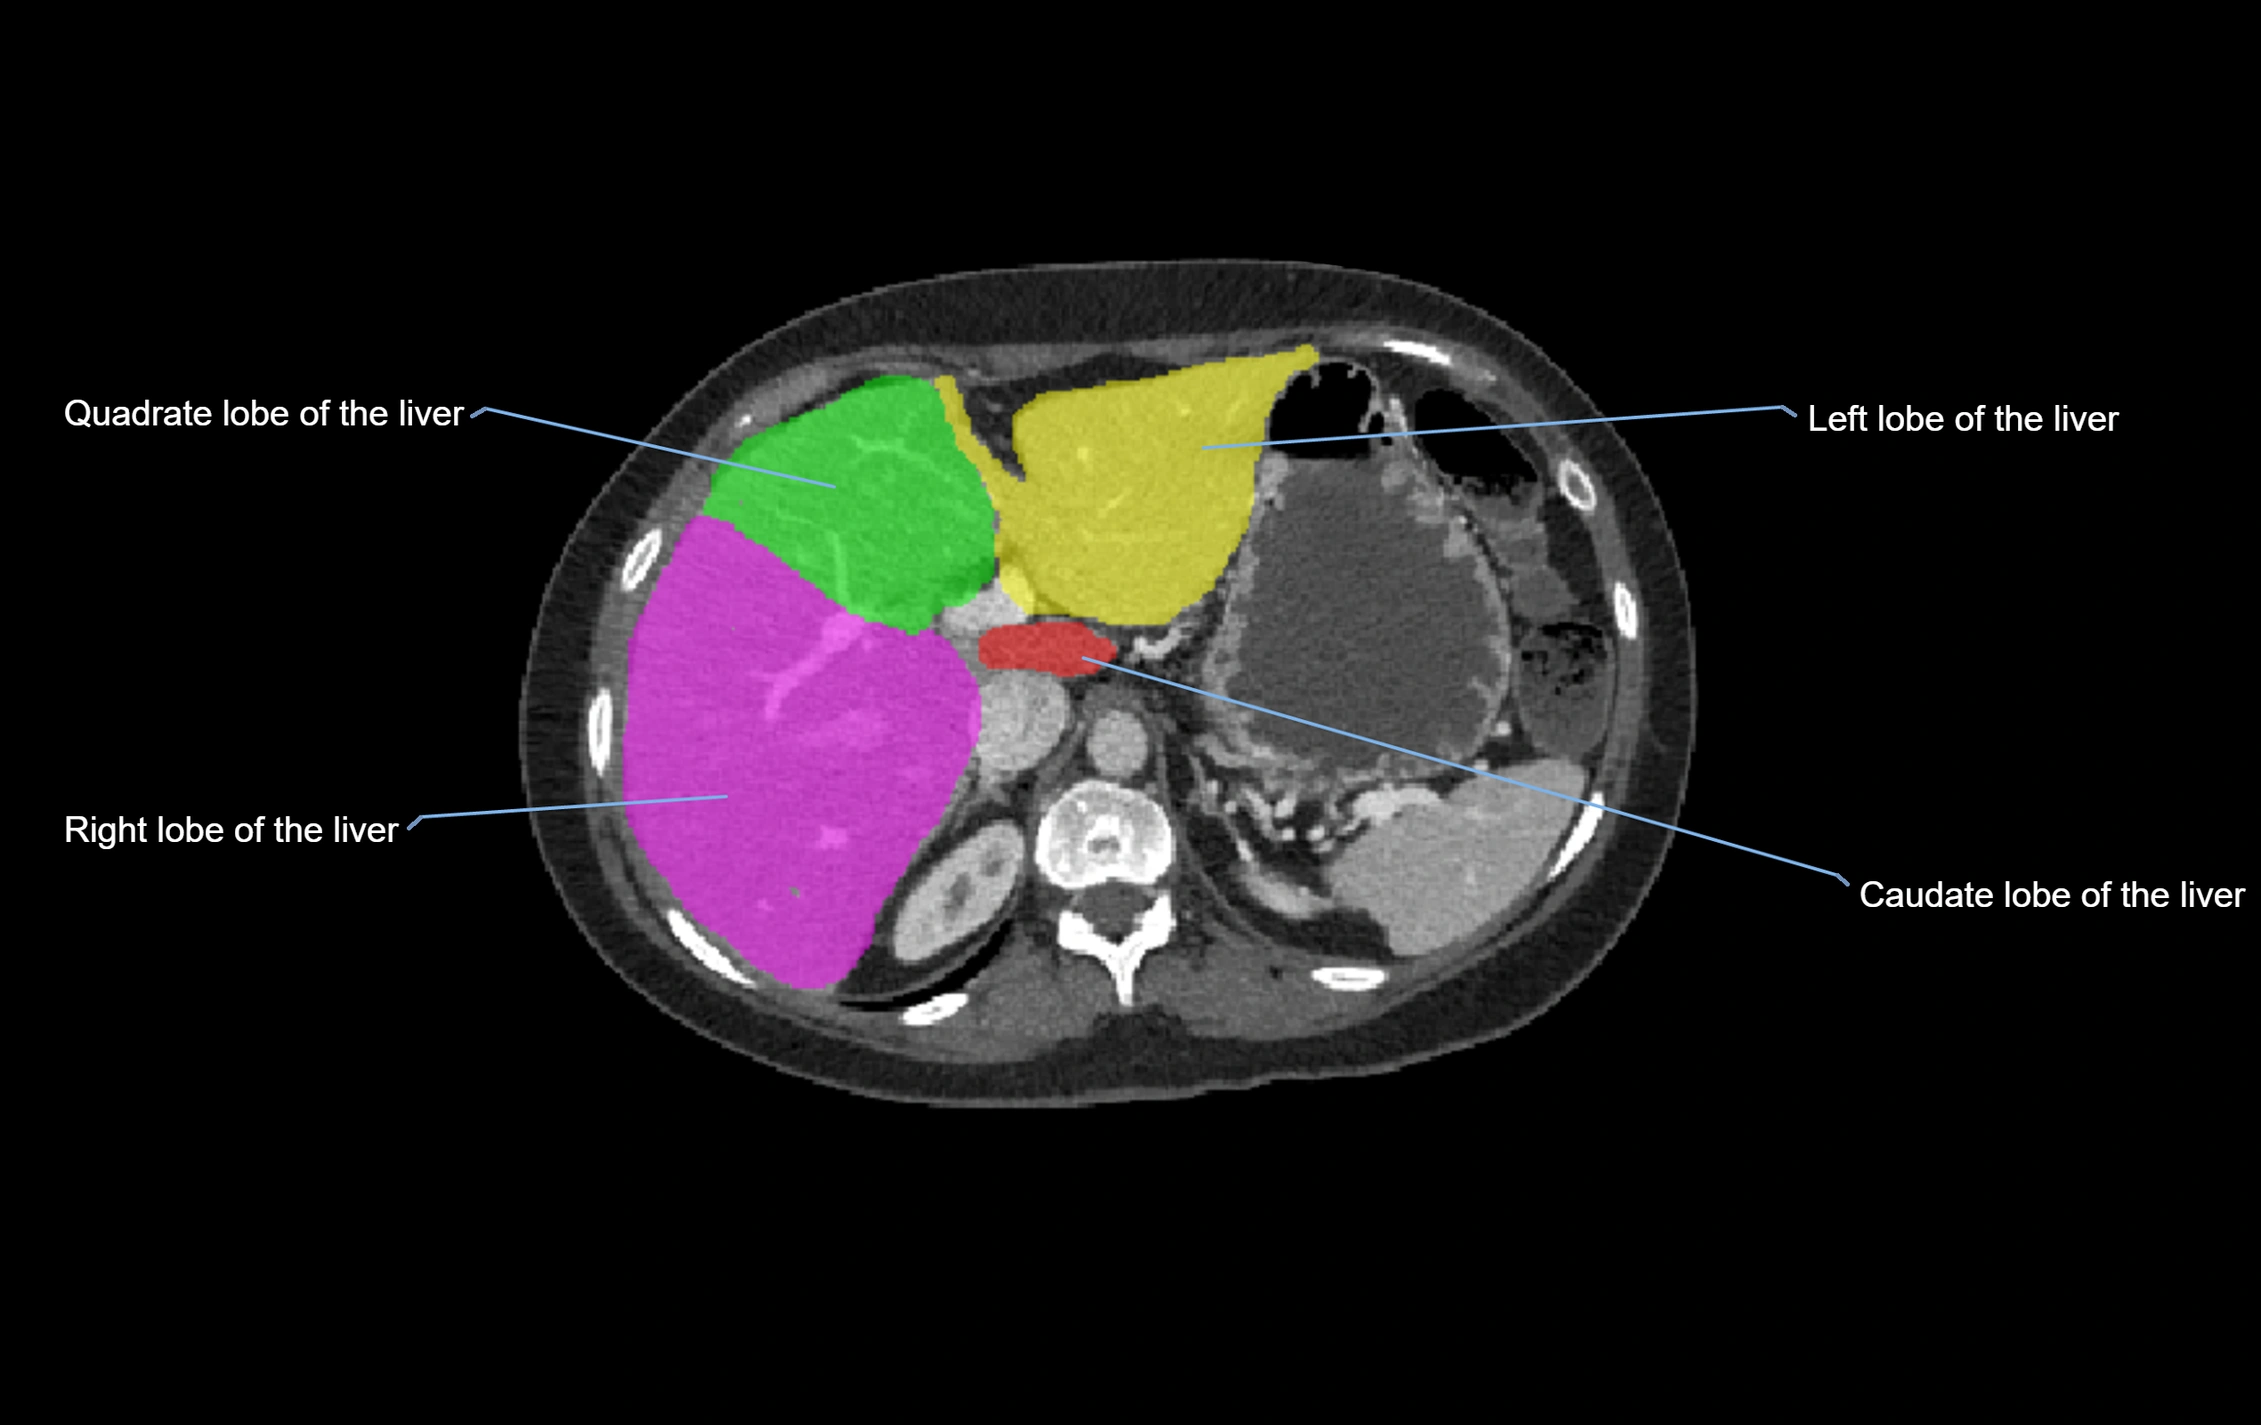

CT Image

image